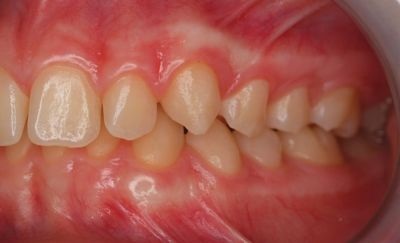

One case posted to the community involved a 13-year-old with a lingually displaced UL3 and plans for full braces, extraction of the primary ULc, and possible exposure and ligation (Figs. 1–5). The treating orthodontist asked: How likely is this canine to correct on its own after extraction?

Fig. 2